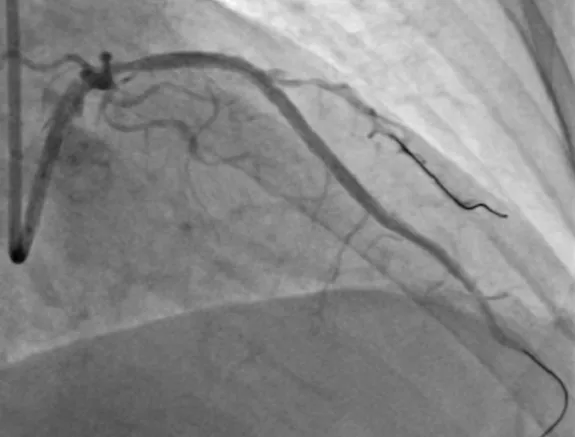

入院后,心血管内科医生为梁阿姨复查了冠脉造影:冠脉三支血管严重狭窄并钙化,原重度狭窄前降支完全闭塞;右冠远段支架通畅,至前降支闭塞远端的侧枝循环良好。

▲左主干近段至前降支近中段钙化明显,中段后100%闭塞